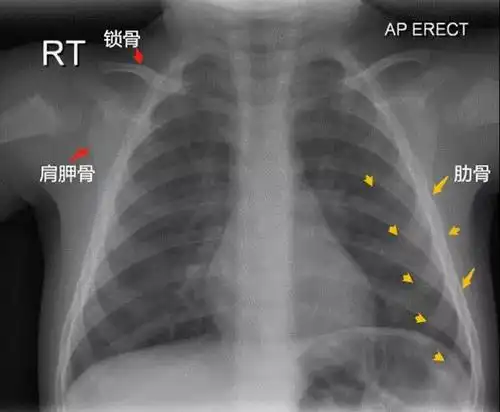

疑难问题,看看这张胸片

儿童肺炎时胸片怎么看呢